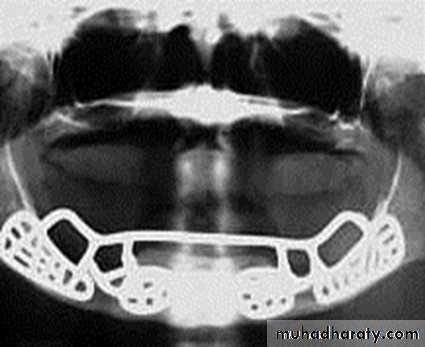

Endosteal or Endosseous implantA. Plate-form implant :

• Blade Implants have a long track record, much longer than the Root form Implants. Their name is derived from their flat, blade-like (or plate-like) portion, which is the part that gets embedded into the bone.

•

These implants are designed for the edentulous lower jaw only and are surgically inserted into the jaw bone in three different areas: the left and right back area of the jaw (the approximate area of the wisdom teeth), and the chin area in the front of the mouth.

It’s indicated in a severely resorbed, edentulous mandible which does not offer enough bone height to accommodate Root form Implants.

It provides a tripodial stabilization of the thin lower jaw and protects it from fracturing.

• Ramus-frame implant

Ramus-frame implant